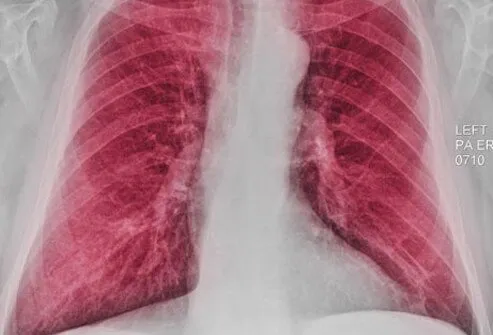

胸部X光

胸部 X 光檢查可能能夠顯示某些COPD患者可能出現的肺部增大(由于過度充氣)。但是,X射線更有用,有助于排除或排除可能導致類似于COPD癥狀的其他問題,例如肺炎。